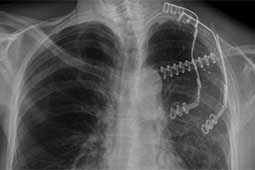

Surgery was performed with curative intent. The patient was positioned supine with the neck fully extended and the head turned away from the tumor. The tumor was approached through the anterior trans-cervical approach described by Dartevelle. This approach allowed us to dissect the subclavian vascular bundle and the nerve roots of the brachial plexus freely, quickly and safely without sacrificing the radical intent of the operation. After assessing the extent of the tumor from inside and outside of the chest, the lateral arches of the first, second and third ribs were cut and removed en-bloc with the surgical specimen (Figure 2). Due to the high risk of de-stabilizing the shoulder girdle after resection of the first three ribs, clavicle division and muscle resection, we reconstructed the chest wall and clavicle using the Stratos™ titanium bars and clips (Strasbourg Thoracic Osteosyntheses System; MedXpert, Heitersheim, Germany) (Figure 3). The chest wall defect and the reconstructed clavicle were covered with polytetrafluoroethylene (PTFE) patches (Figure 4).

During follow-up the respiratory function and dynamics were optimal and there was no mechanical failure of the titanium bars and clips. The surgical margins were free from disease, and after 6-months follow-up the patient is free from disease recurrence.